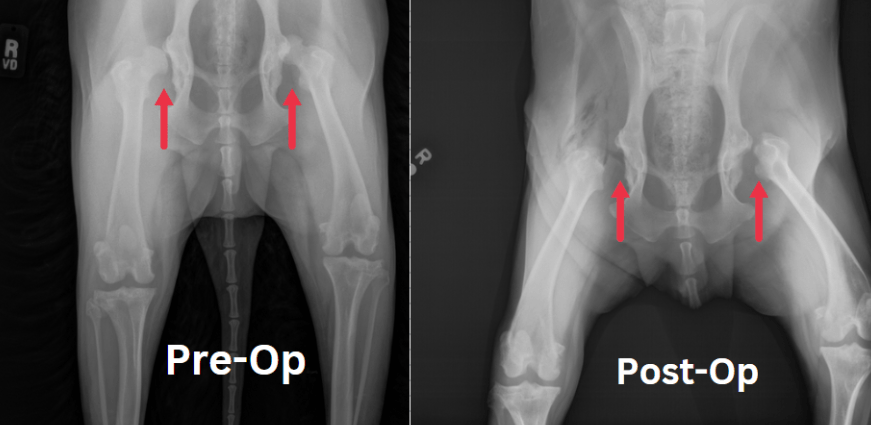

A Cranial Cruciate Ligament (CCL) rupture is a common orthopedic issue in dogs, particularly in certain breeds. The CCL is equivalent to the anterior cruciate ligament (ACL) in humans and plays a crucial role in stabilizing the knee joint. The rupture or tearing of the CCL is often associated with conditions such as ligament degeneration, trauma, or a combination of both.

In the realm of orthopedic injuries in dogs, the cranial cruciate ligament (CCL) tear stands out as the most prevalent traumatic issue, affecting dogs of all ages and breeds. By the late 1990s, Tibial Plateau Leveling Osteotomy (TPLO) had emerged as a widely adopted technique for addressing this condition. Its popularity soared, particularly due to its remarkable success in effectively managing CCL tears, especially in large and highly active canine patients.

This surgical technique aims to redefine the relationship between the femur and tibia, addressing the instability induced by CCL rupture and mitigating future joint complications.